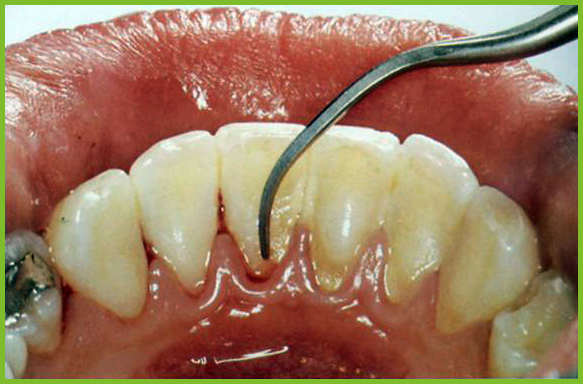

Auch bei bester häuslicher Mundpflege bleiben Beläge auf den Zähnen zurück - vor allem in den Zahnzwischen-räumen. Dort tummeln sich Millionen von Bakterien, die Karies, Parodontitis, unangenehmen Mundgeruch und diverse Krankheiten verursachen können.

Zahnbürste und Zahnseide haben ihre Grenzen, denn sie erreichen nicht die in den tiefen Zahnfleischtaschen hartgewordene Zahnbeläge und Bakterienherde.

Mit der PZR können auch tiefsitzende Zahnbeläge, sowie Bakterienherde in schwer zugänglichen Zwischenräumen und Nischen beseitigt werden.

Gegen hartnäckige bakterielle Zahnbeläge - die Hauptverursacher von Karies und Parodontitis - kommt auch die gewissenhafteste häusliche Zahnpflege nicht immer an. Deshalb gibt es die professionelle Zahnreinigung. Mit ihr werden sämtliche harten und weichen Beläge sowie Bakterien auch in schwer zugänglichen Zwischenräumen und Nischen beseitigt.